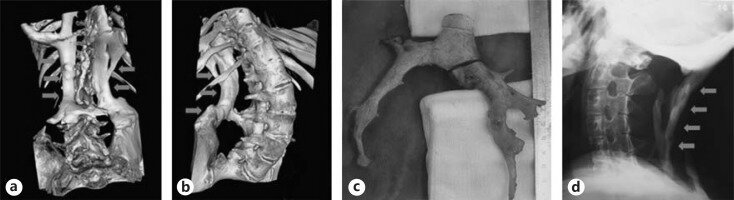

Позвонковые наросты кораллообразной формы:

14 апреля 1736 года в госпиталь св.Варфоломея пришел мальчик. Его походка была немного странной, но передвигался он самостоятельно. Ему было 14 лет и без детального осмотра он казался вполне здоровым. Мальчик спросил врача приемного отделения: “Что нужно сделать, чтобы избавиться от наростов?”. “Каких наростов?” – ответил доктор. Дальнейшие исследования описывают найденные у мальчика кораллообразные наросты толщиной, не превышающей пенни, и отходящие от позвонков, начиная с шеи и до крестцового отдела, а также от каждого ребра – соединяя их вместе, наросты формировали корсет, мешавший ребенку двигаться, нагибаться, вращать шеей. Тогда эти наросты наспех сравнили с конкрементами, которые образуются у человека в желчном и мочевом пузырях, да и вообще много где… Мальчика послали к Джону Фрекке, который как раз и увлекался «камнеобразованием». Если бы не его любопытство, возможно этот случай бы также не дошел до нас. Но доктор стал с интересом следить за пациентом, хотя помочь ему ничем не мог. За время исследований и наблюдений был отмечен быстрый прогресс заболевания.

Сложно сказать, что бы стало с такими пациентами на территории Европы в ранее Средневековье, эпоху религиозных войн или период расцвета инквизиции. Так, например, в 1744 году для медицинского осмотра тела, напугавшего врачей, привлекли даже служителей церкви. Преподобный Дин Копинг вместе с епископом Робертом Р.Р. и Чарльзом Смитом осматривали скелет умершего от фибродисплазии, испытывая одновременно религиозный трепет и собственное мужество на прочность. Из известного описания мы можем выделить следующие моменты: весь скелет представляет из себя цельную, не распадающуюся и несгибаемую структуру. Лопатки срослись в пластину, от костей бедер отходят гребни и шипы, напоминающие побеги коралла или ветви жуткого растения, длинной они достигают от 8 до 9 дюймов. Из задней части пяточных костей вырастают шпоры. Массивные деформированные челюсти удалось открыть только ножом. Болезнь настигла мужчину в возрасте 18 лет и к 60 забрала его жизнь.

Сросшиеся в единую пластину кости спины и представитель оленьковых: